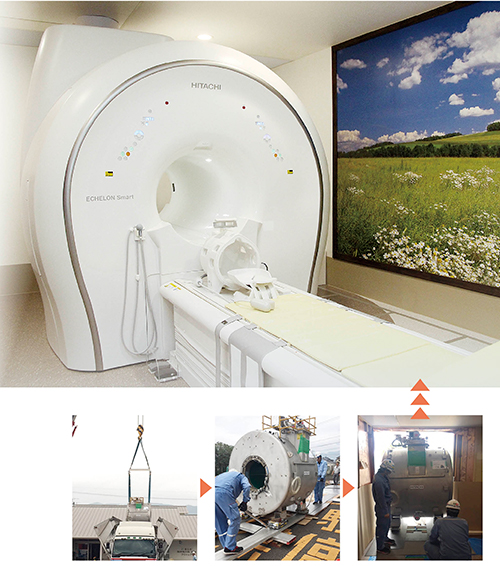

佐賀県小城市のまえだ脳神経外科・眼科クリニックは2017年10月,永久磁石型0.4TオープンMRI「APERTO Inspire」を1.5T超電導MRI「ECHELON Smart」に更新した。前号(『磁遊空間』Vol.35/2017年8月発行) では,更新に当たってECHELON Smartへの期待について,前田健二院長,谷水久夫技師にインタビューした。更新からもうすぐ1年となる同クリニックを再訪し, ECHELON Smartの臨床使用の実際について取材した。

2008年に「メディカルモールおぎ」(佐賀県小城市)に開業したまえだ脳神経外科・眼科クリニックは,永久磁石型0.4TオープンMRI「APERTO Inspire」を導入し,脳神経領域を中心に活用してきた。2015年にAPERTO Inspireをアップグレードし,画質や撮像スピードが向上。翌年には,さらに高度なMRI検査をめざして高磁場MRI導入に向けた検討が始まった。そして採用されたのが,限られたスペースにも導入が可能な1.5T超電導MRI「ECHELON Smart」だ。

MRI検査休止期間を経て,ECHELON Smart は2017年10月1日に稼働を開始した。休止期間中はCT検査や近隣病院への紹介で対応していたが,前田院長は,「歩いて来院するような軽症の急性期脳梗塞はCTではわかりにくいため,検査休止期間はMRIの必要性を改めて痛感しました。装置更新では,APERTO Inspireが入っていた検査室を増改築することなくECHELON Smartを設置でき,非常に満足しています」と話す。

ECHELON Smartガントリ搬入の様子